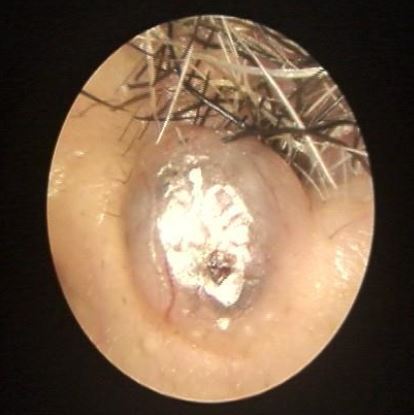

治療前左側(cè)鼻塞流涕3月入院,電子鼻咽鏡和CT發(fā)現(xiàn)鼻腔內(nèi)發(fā)現(xiàn)鼻腔鼻竇內(nèi)有腫物,并有霉菌團(tuán)塊信號(hào)影治療后治療后150天術(shù)中證實(shí)鼻竇內(nèi)翻性乳頭狀瘤和霉菌團(tuán)塊。術(shù)后鼻塞流涕癥狀消失,術(shù)后5月復(fù)查MRI鼻腔鼻竇腫瘤病灶完全清除,沒(méi)有復(fù)發(fā)。